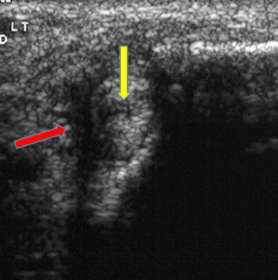

What does the arrow indicate? | A cleft (tear) in the tendon |

What does the red arrow show? What does the yellow arrow show? | Red arrow = fluid Yellow arrow = tendon tear |